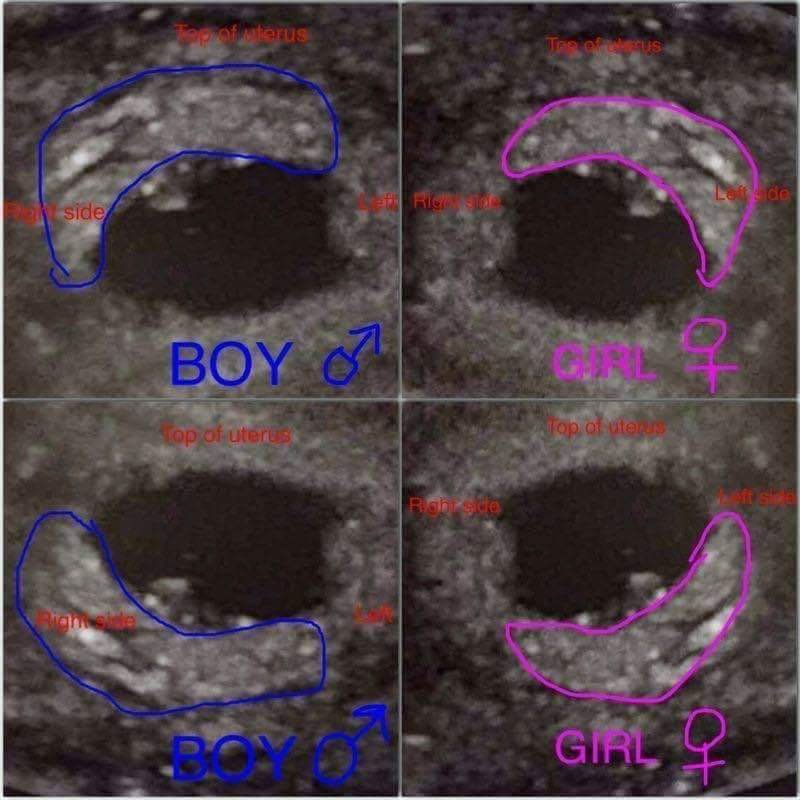

прилагам още един метод за пола, синът ми отговаряше, сега това бебче е в позицията на момиченцата.. Дано да е вярно 😁😁😁 прилагам и доказателство